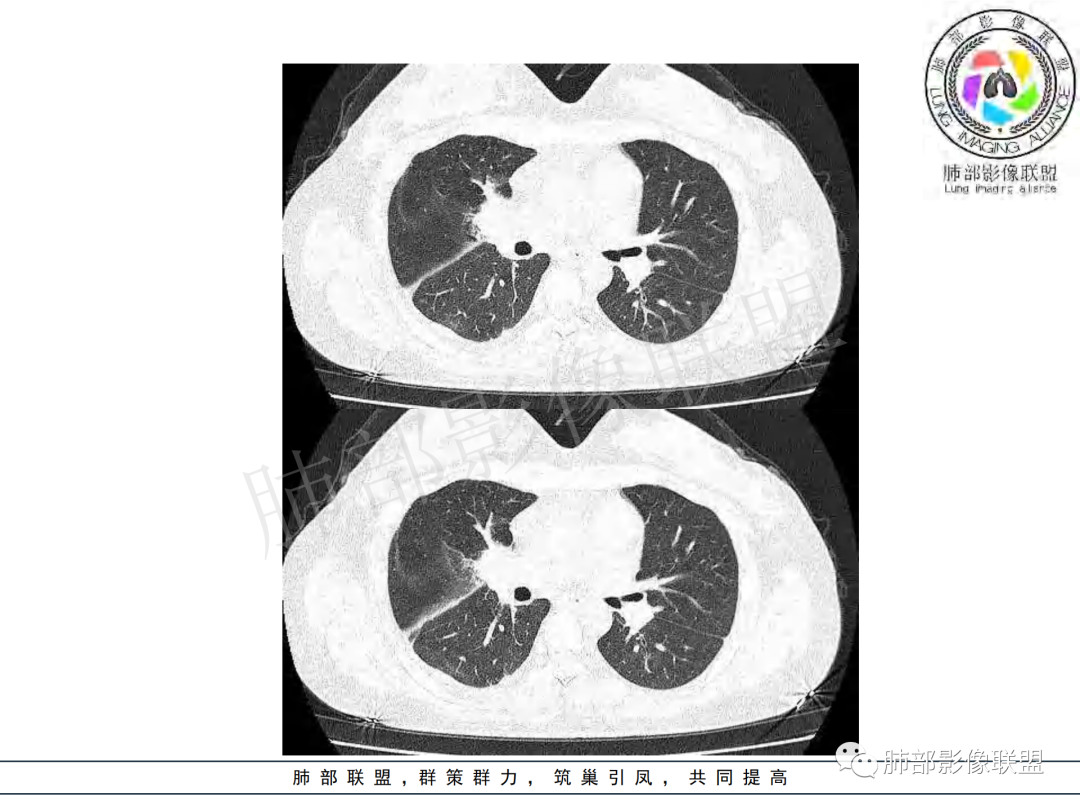

右肺肺门旁肿块,右肺中间段支气管腔内结节,增强强化不均;纵隔多发淋巴结环形强化,右侧少量胸腔积液,临床发热入院,考虑结核,鉴别肿瘤。

纵隔多组及右侧肺门多发肿大淋巴结,部分融合,不均匀强化,内见斑片状坏死区及环状强化,后者坏死边界尚清晰,肺门区肿大淋巴结与肺组织边界不清,年轻女性,8个月病史,发热首发症状,考虑淋巴结核并向肺内侵及(破溃?),鉴别淋巴瘤

女,20,病程长达8月,发热、胸痛、右侧胸腔积液病史。胸部CT:右肺门旁不规则肿块影,右中间支气管腔内结节,纵隔多发淋巴结肿大;强化不均匀,灶性坏死灶,环形强化;右侧少量胸腔积液并局部肉芽肿样突起。年轻女性,长病程,多部位,考虑慢性炎症,结核?鉴别肿瘤。

年龄和病史比较符合结核,但是中叶支气管好像堵塞了,管腔有新生物,恶性肿瘤也不能排除,做一个支气管镜应该能确诊

支气管腔内有占位,肺门区病灶和胸膜结节明显强化,淋巴结环状强化为主,部分明显强化,年轻女性,首先考虑结核,鉴别腺癌

青年女性,发热、胸痛、右侧胸腔积液病史,病程8个月。曾多次抗炎后均有好转。CT:右肺门旁肿块影,双侧胸膜结节,纵隔多发淋巴结肿大,边缘模糊;增强渐进性明显强化,纵膈淋巴结较彻底坏死灶,边缘环形强化。考虑结核,鉴别恶性肿瘤。

女性,20岁。高热、畏寒。右肺上叶近肺门区不规则肿块,周围斑点、片小结节影伴肿大淋巴结,肿块包绕并突入右主支气管腔内,增强后肿块不均匀强化,淋巴结环形强化中心低密度,考虑结核。

本例患者,年轻女性,慢性病程,多次抗感染治疗效果不佳,实验室检查示白细胞及中性粒细胞不高,不支持普通细菌感染,虽然肺泡灌洗液X-Pert检测阴性,结合患者胸部CT结核感染亦不能排除,胸部CT主要表现为右侧肺门及纵隔淋巴结肿大,仔细观察不难发现右中间支气管内新生物凸向管腔内,增强扫描,右肺门(10R)及纵隔淋巴结(2R,4R)明显不均匀强化,内部呈不规则低密度无强化区,被周边高强化区包绕(环形强化)的特点,首先应当想到纵隔淋巴结结核诊断。淋巴结分布亦不符合肺部恶性肿瘤迁徙途径。